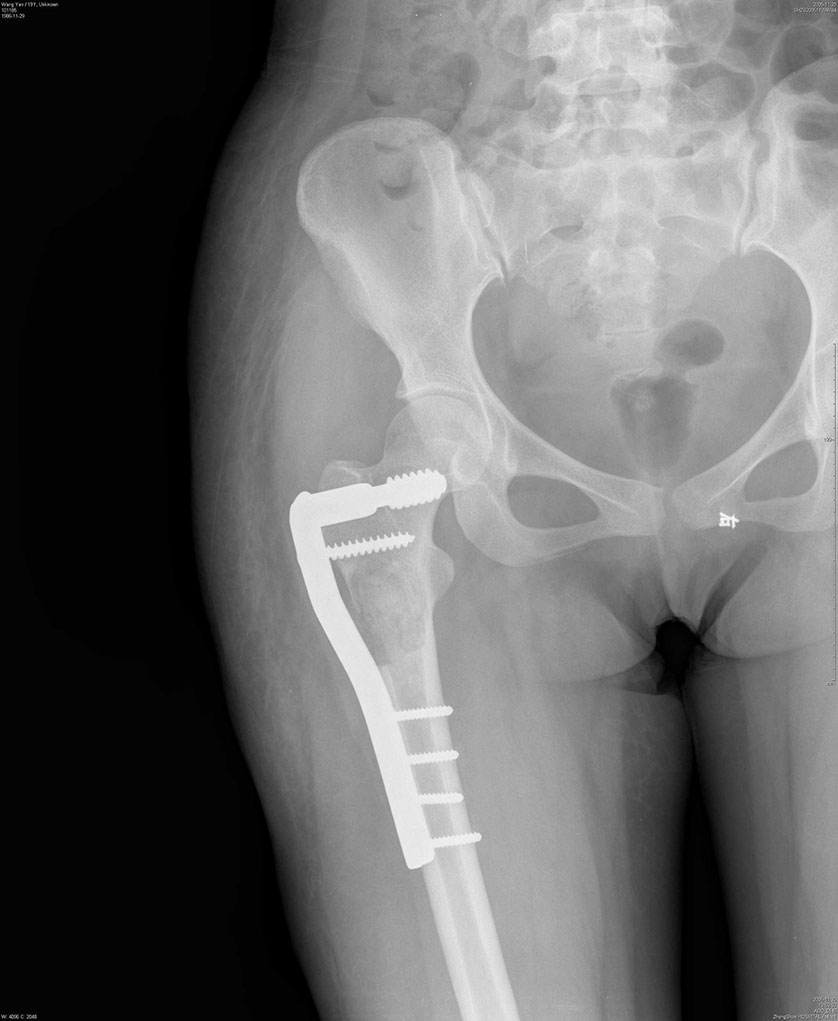

王*,女性,因右股骨骨囊肿,于2005年11月行囊肿刮除,同种异体骨颗粒植入,股骨近端DHS钢板螺钉内固定术后,术后1年和2年随访,骨愈合良好,内固定拔除。